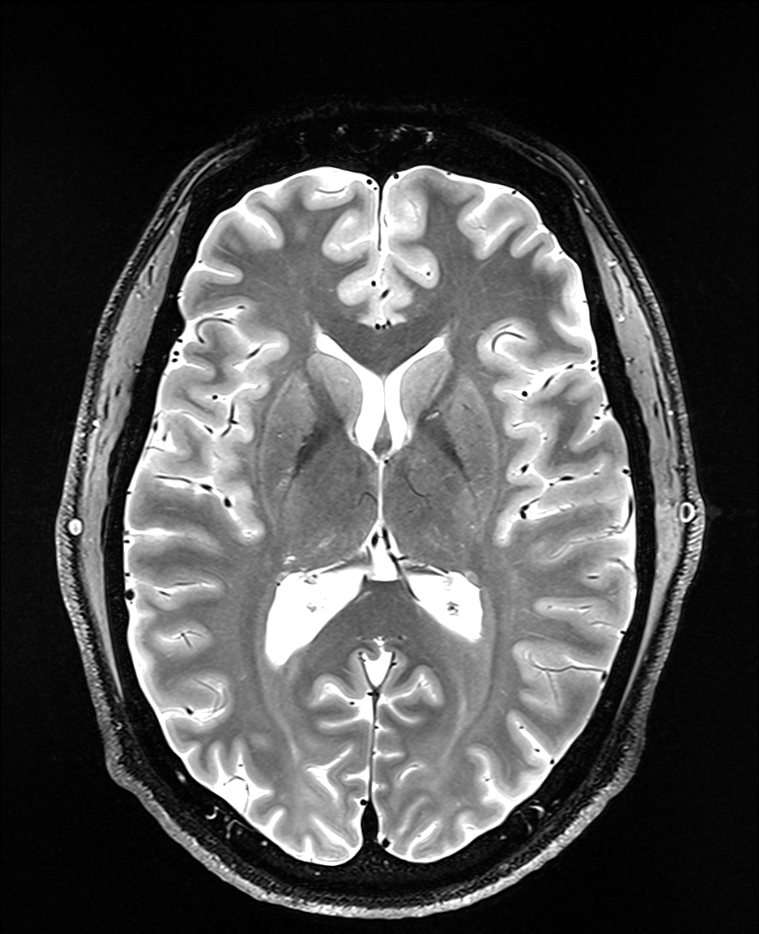

• La tâche est réalisée pendant que les participants sont soumis à une imagerie cérébrale (IRMf). Nous cherchons à déterminer si le fait d’anticiper et d’acquérir des connaissances intéressantes active des régions cérébrales liées à la récompense similaires à celles sollicitées par les odeurs agréables et l’argent.

• À l’aide de méthodes d’analyse avancées, nous vérifions si les schémas d’activité cérébrale observés face à des odeurs agréables et à l’argent permettent de prédire les réactions cérébrales face à des connaissances intéressantes, et inversement.